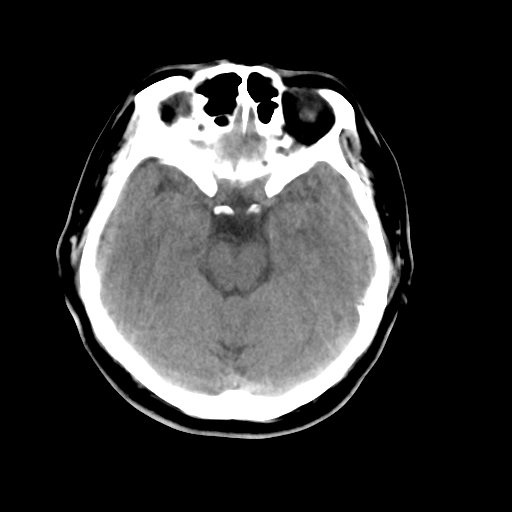

以下是引用liuyue在2008-4-28 13:34:00的发言:[br]右额叶条状高密度影,边缘清楚,周围未见水肿及占位.[br]考虑:血管畸形可能性大.[br]建议:强化ct扫描或mri检查.除外脑回钙化.

以下是引用论黑辩白在2008-4-28 12:53:00的发言:[br]右额叶局限性脑萎缩,右额叶见条状高密度影,建议mri进一步检查。[br][br][本贴已被 论黑辩白 于 2008-4-28 13:08:16 修改过]